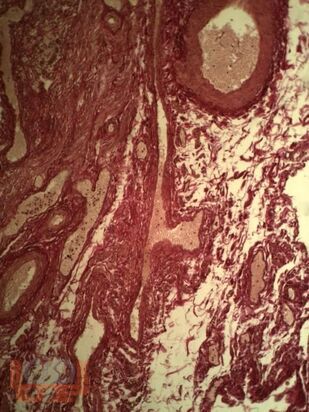

Апоплексия яичника

В монографии изложены данные отечественных, зарубежных авторов, результаты собственных исследований, посвященных причинам и механизмам апоплексии яичника у женщин и методам реабилитации для предупреждения рецидива заболевания. Представлены собственные результаты клинико-лабораторных, инструментальных методов исследования, а также опыт применение квантовой терапии в раннем послеоперационном периоде у пациенток с апоплексией яичника.